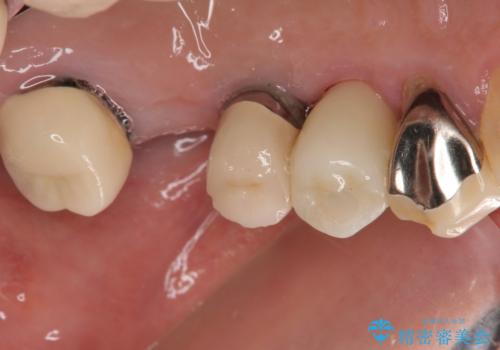

従来は4ヶ月ほど待機してからの埋入が一般的でしたが、歯肉の炎症が落ち着いた時点で速やかに埋入できるようになり、4ヶ月の短期間で治療を終えることができました。

- 4ヶ月

- 2-5回